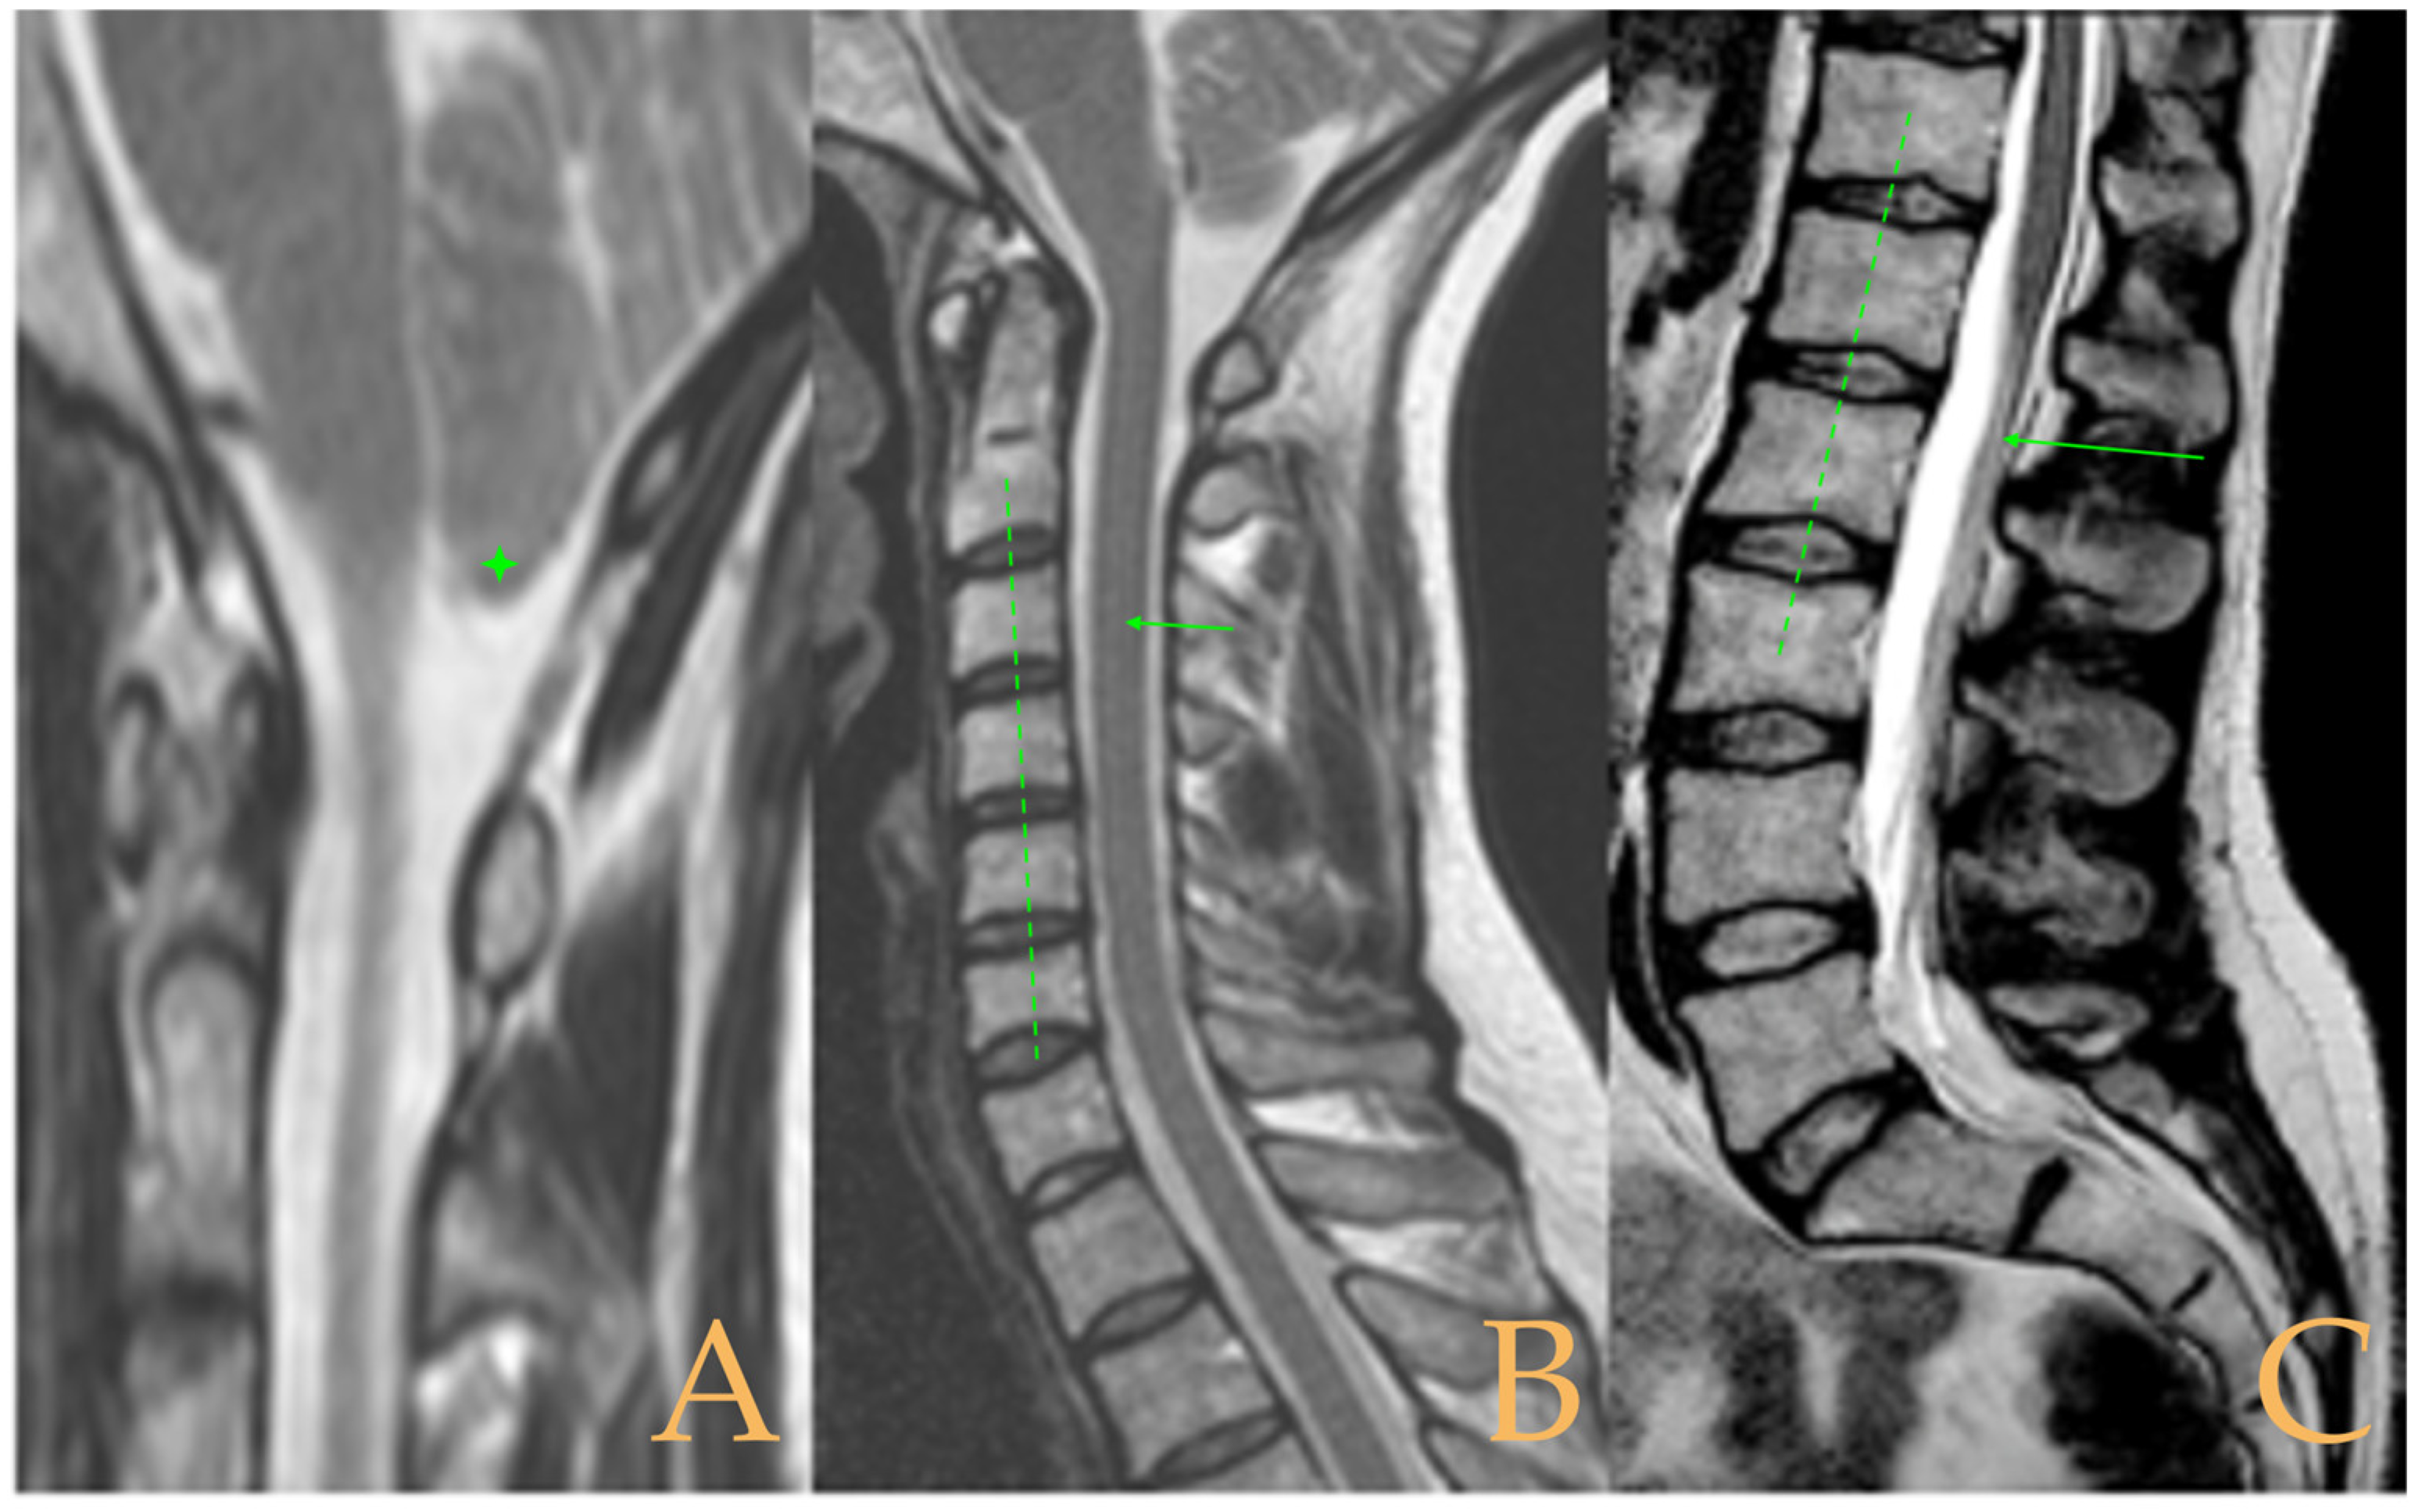

Magnetic resonance imaging showed a slight descent of the cerebellar tonsils, multiple diseased discs, and conus medullaris at the level of the middle third of the L1 vertebra. The X-ray images of the entire spine revealed a mild dextroconvex thoraco-lumbar scoliosis with 5° Cobb angle (Figure 1).

Figure 1. Imaging of patient 1. A: Mild descent of the cerebellar tonsils (arrows); B: multiple disc disease (arrows) and straightening of the cervical spine (interrupted line); C: conus medullaris at the middle third of L1 (arrow); and D: mild deviation of the vertebral column (interrupted lines).